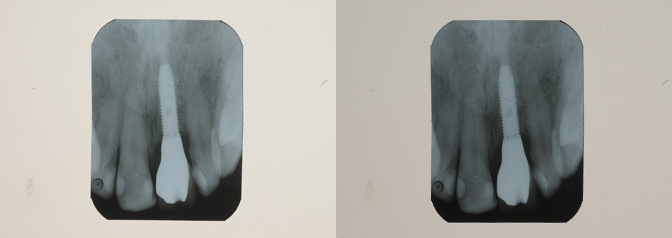

011:S.M.さん 前歯部インプラント

前歯が折れてしまい、とても困って来院されました。

両隣の歯が健康で削らなくてすむのなら出来るだけ削ずらない方が長い人生の中では歯が長持ちします。この様な場合にはインプラントを用いるのが一番よい適応症と考えます。

レントゲン